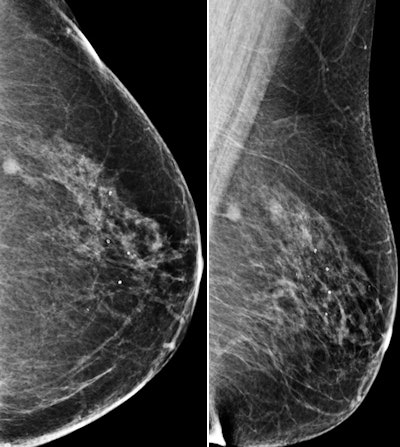

The study included 340 women with 353 lesions that were found at screening mammography (198) or ultrasound (155). The lesions were rated BI-RADS category 4 after appropriate conventional workup between June 2010 and January 2013. All of the women underwent standard dynamic contrast-enhanced MR imaging (Radiology, February 2015, Vol. 274:2, pp. 343-351).

Among the 198 mammography findings, 71 were masses, 34 were asymmetric densities, 15 were architectural distortions, and 78 were clustered microcalcifications. Of the 155 ultrasound findings, 115 were masses and 40 were nonmass lesions.